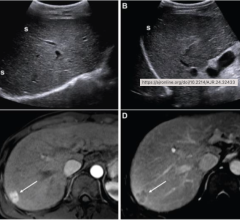

Despite decades of progress in breast imaging, one challenge continues to test even the most skilled radiologists ...

March 2, 2026 — Ultrasound AI, a provider of artificial intelligence applications for medical imaging, has received FDA ...

Feb. 26, 2026 — AS Software, a provider of specialty-focused ultrasound reporting solutions, has announced that the U.S ...